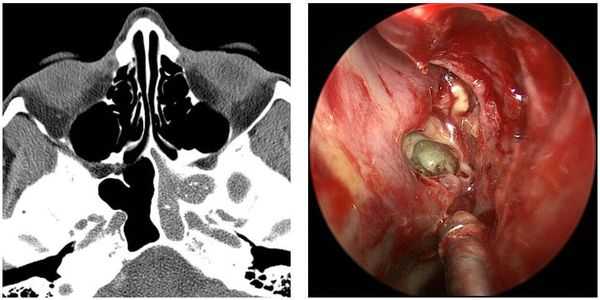

в) Диагностика полипов в носу. Диагноз ставят на основании типичной клинической картины, выявляемой при передней риноскопии: наличие одиночного или множественных тусклых, полупрозрачных, беловато-желтых массивных образований с гладкой поверхностью, подвижных при исследовании зондом и обычно локализующихся в среднем носовом ходе или хоане. Полипы обычно бывают двусторонними. Из других исследований следует отметить назальную эндоскопию, КТ, определение уровня С-реактивного белка, цитологическое исследование и аллергологические пробы.

P.S. При полипозе носа часто наблюдается образование полипов также в околоносовых пазухах, поэтому последние всегда необходимо исследовать рентгенологически, а если возможно, то и эндоскопически.